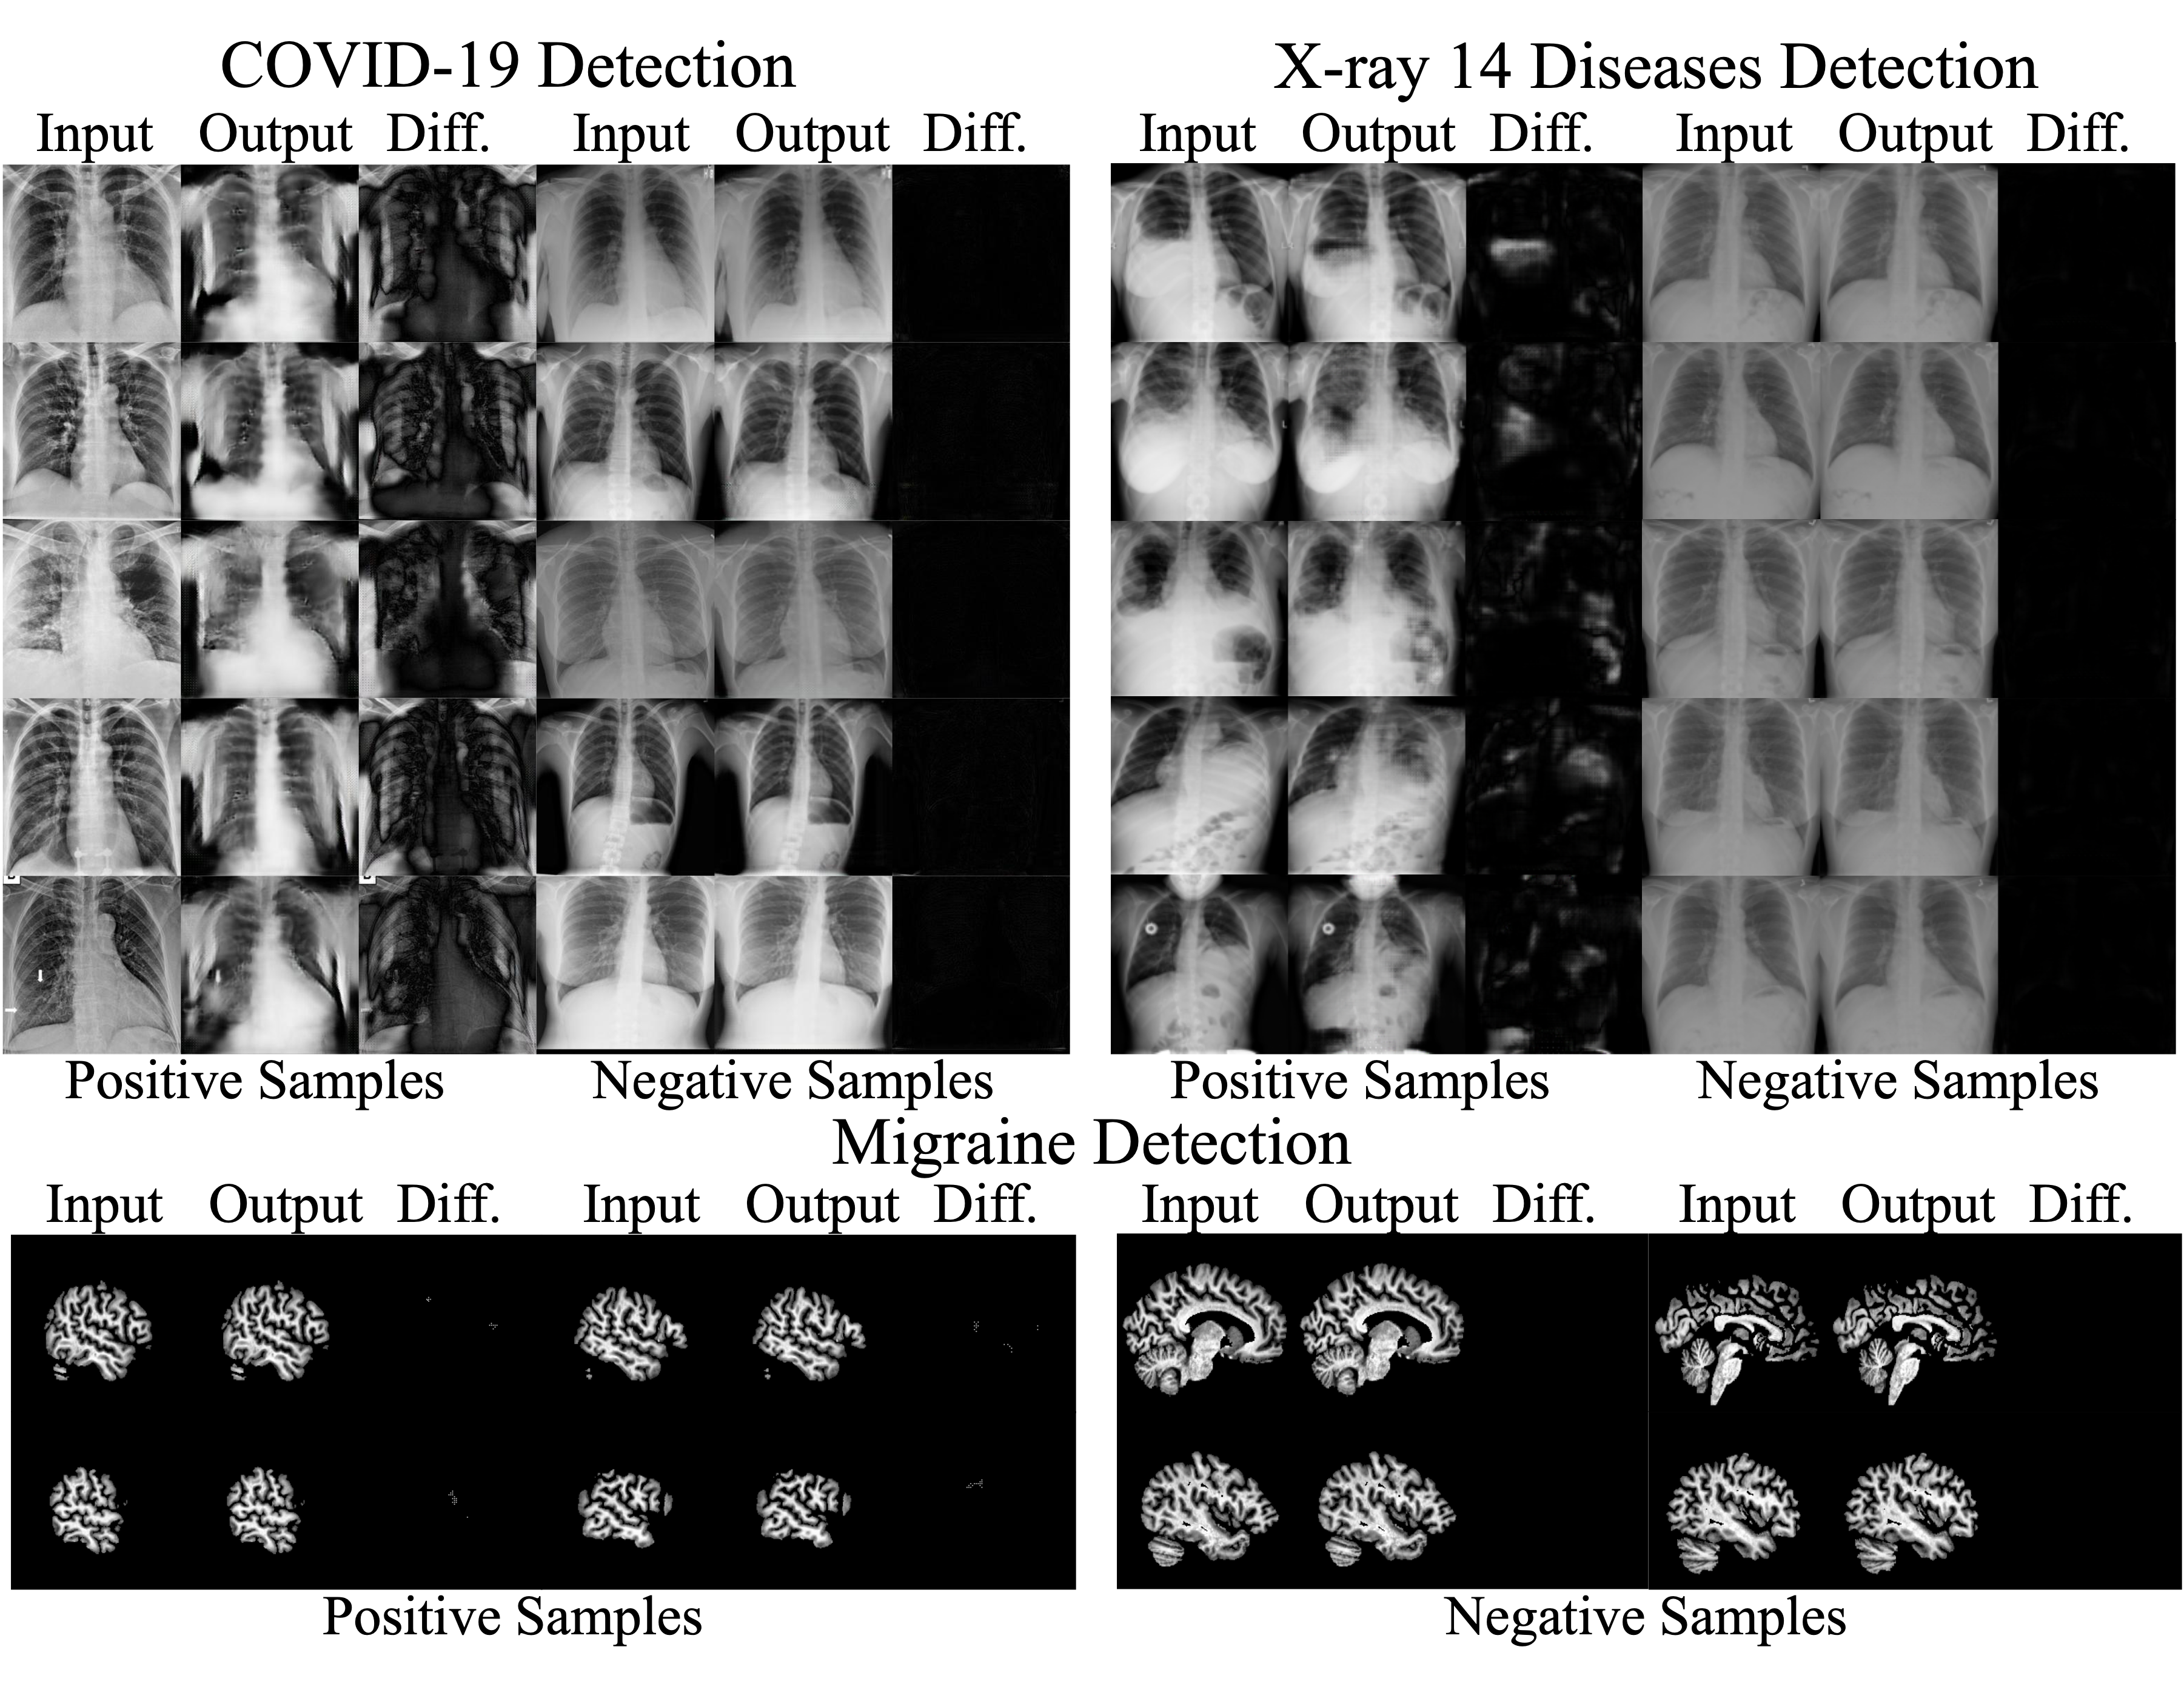

Results. The top section in Tab. 1 summarizes the COVID-19 detection results. As seen, HealthyGAN achieves COVID-19 detection AUC of 0.84 outperforming all the conventional methods by a large margin. It also achieves the best precision, specificity, and F1 scores of 0.76. In contrast, f-AnoGAN, the top performing among the competing methods, achieves an AUC score of only 0.64 which is 0.20 points lower than the proposed HealthyGAN. f-AnoGAN achieves precision, recall, specificity, and F1 scores of 0.55, 0.53, 0.56, and 0.54, respectively. Fig. 3 shows qualitative results of COVID-19 detection by HealthyGAN.

Results. The middle section of Tab. 1 summarizes the 14 diseases detection results. As seen, HealthyGAN achieves the best detection AUC score of 0.56 while f-AnoGAN performs the second best with an AUC score of 0.55. They both achieve precision, recall, specificity, and F1 scores of 0.55. Fig. 3 contains qualitative results of the 14 diseases detection by HealthyGAN.

Refer to caption

Figure 3: Qualitative results of COVID-19, Chest X-ray 14 diseases detection, and Migraine detection by HealthyGAN. As seen, HealthyGAN has resulted in a high response in the difference maps for positive samples compared to the negative samples.

Results. The last section of Tab. 1 summarizes the results for migraine detection. HealthyGAN outperforms all the conventional methods by achieving an AUC score of 0.75. It also achieves the best precision, recall, specificity, and F1 scores of 0.78, 0.70, 0.80, and 0.74, respectively. In contrast, the top performing conventional method, Ganomaly, achieves AUC, precision, recall, specificity, and F1 scores of only 0.70. Fig. 3 shows qualitative results of HealthyGAN.